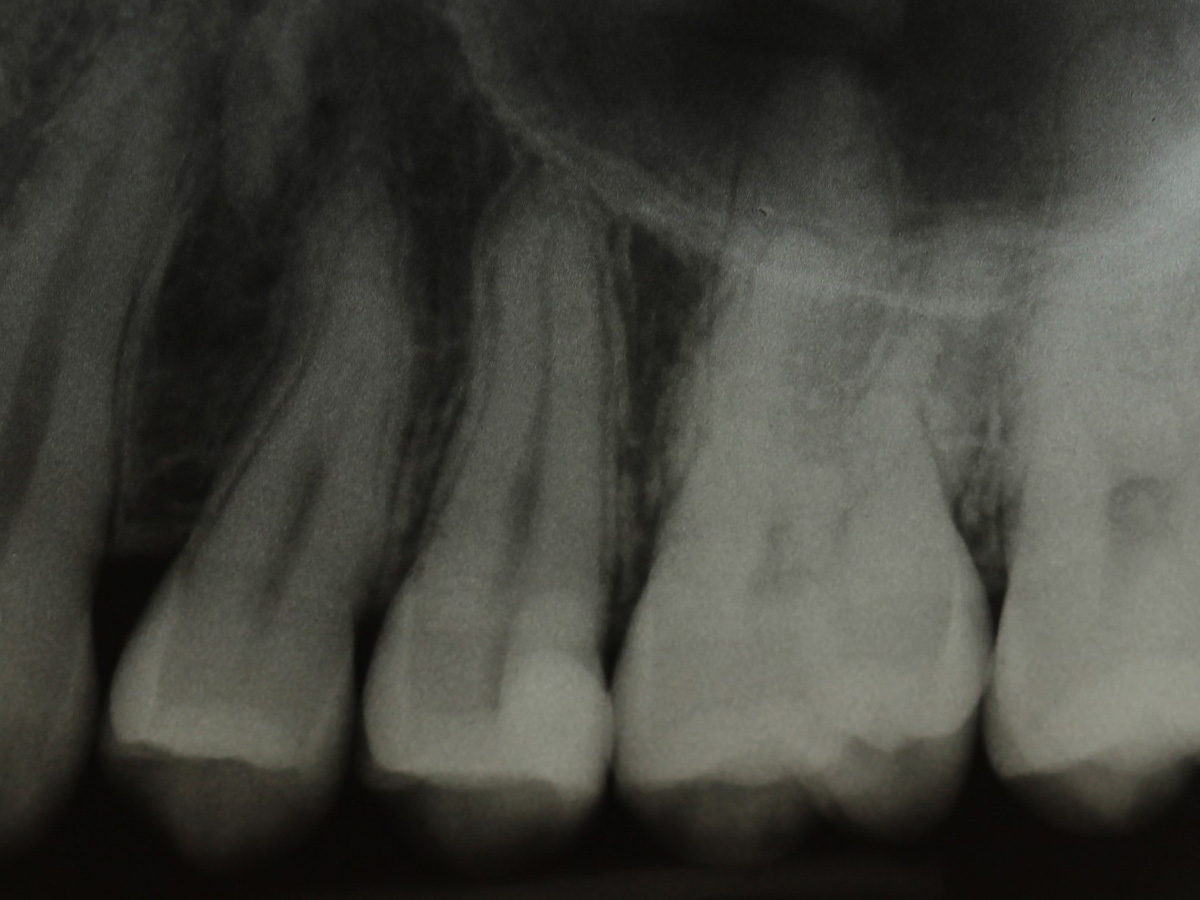

Abbildung 2

Bissflügelröntgenaufnahme